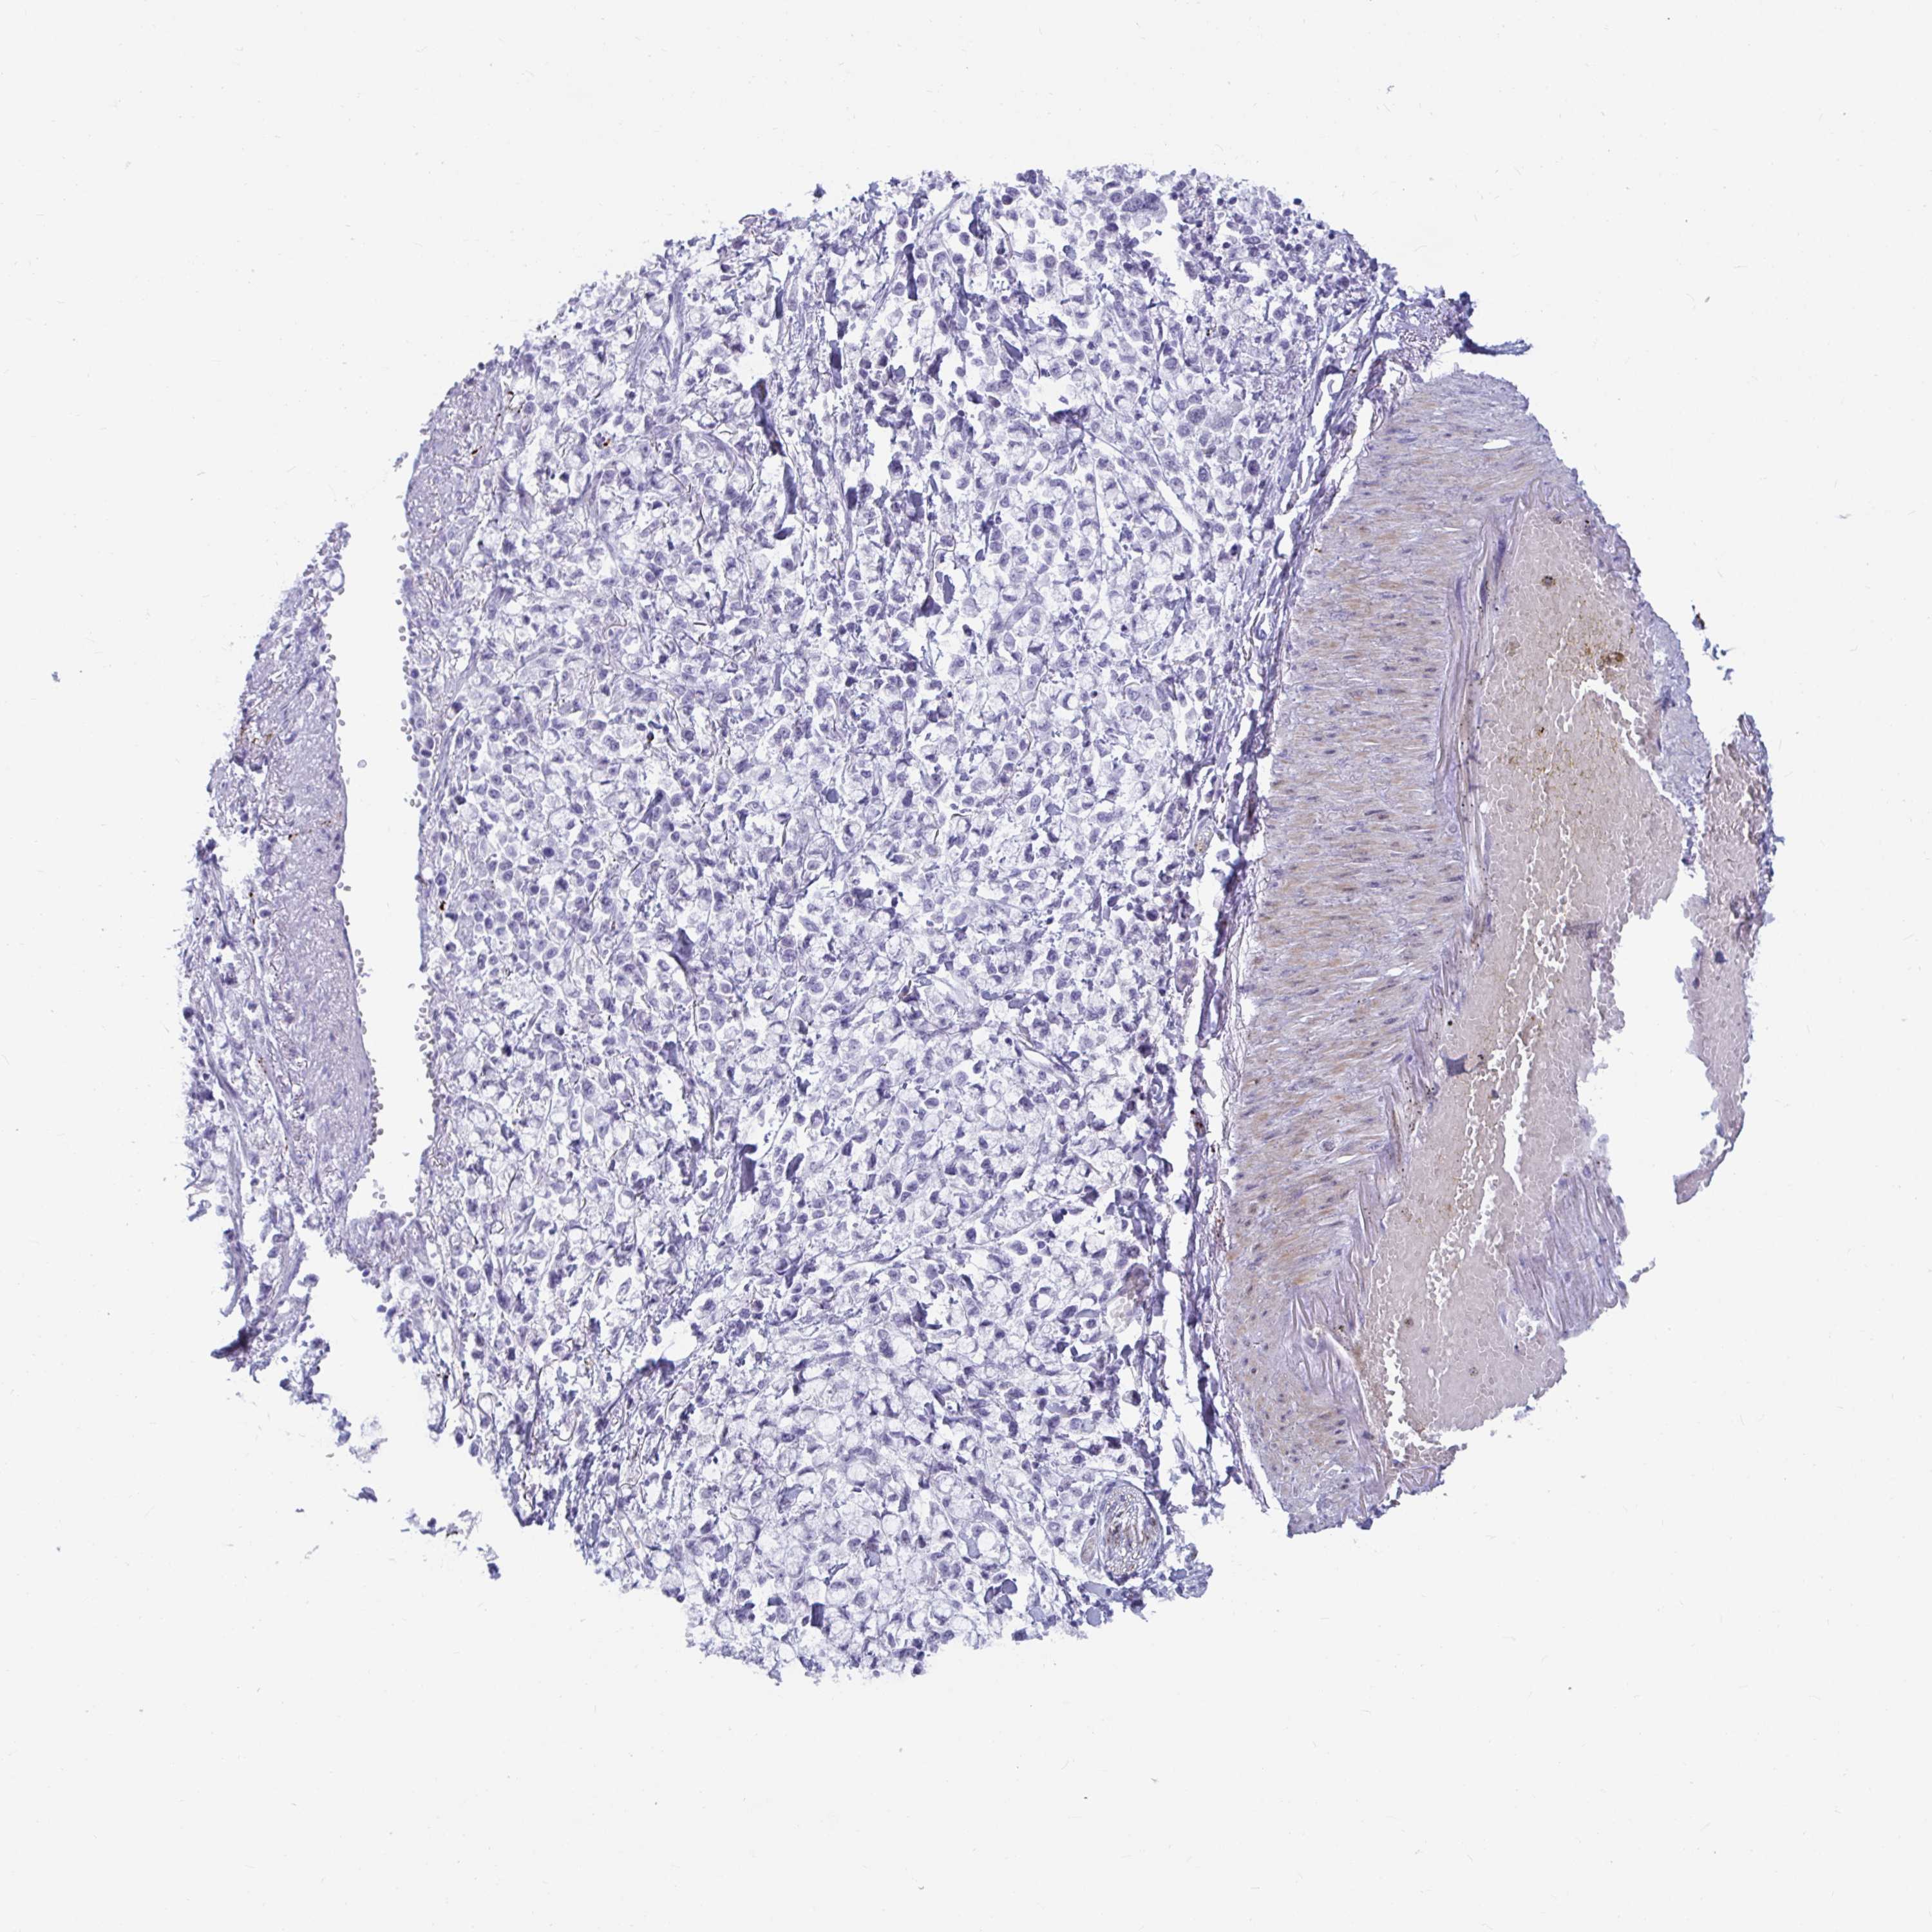

STOMACH CANCER - Protein expressioni

A mouse-over function shows sample information and annotation data. Click on an image to view it in a full screen mode. Samples can be filtered based on level of antibody staining by selecting one or several of the following categories: high, medium, low and not detected. The assay and annotation is described here.

Note that samples used for immunohistochemistry by the Human Protein Atlas do not correspond to samples in the TCGA dataset.

Antibody stainingi

Antibody staining in the annotated cell types in the current human tissue is reported as not detected, low, medium, or high, based on conventional immunohistochemistry profiling in selected tissues. This score is based on the combination of the staining intensity and fraction of stained cells.

Each image is clickable and will lead to virtual microscopy that enables deeper exploration of all samples and also displays staining intensity scores, fraction scores and subcellular localization as well as patient and tissue information for each sample.

Antibody CAB016733

Staining

High

Medium

Low

Not detected

Intensity

Strong

Moderate

Weak

Negative

Quantity

>75%

75%-25%

<25%

None

Location

Nuclear

Cytoplasmic/membranous

Cytoplasmic/membranous,nuclear

Adenocarcinoma, NOS